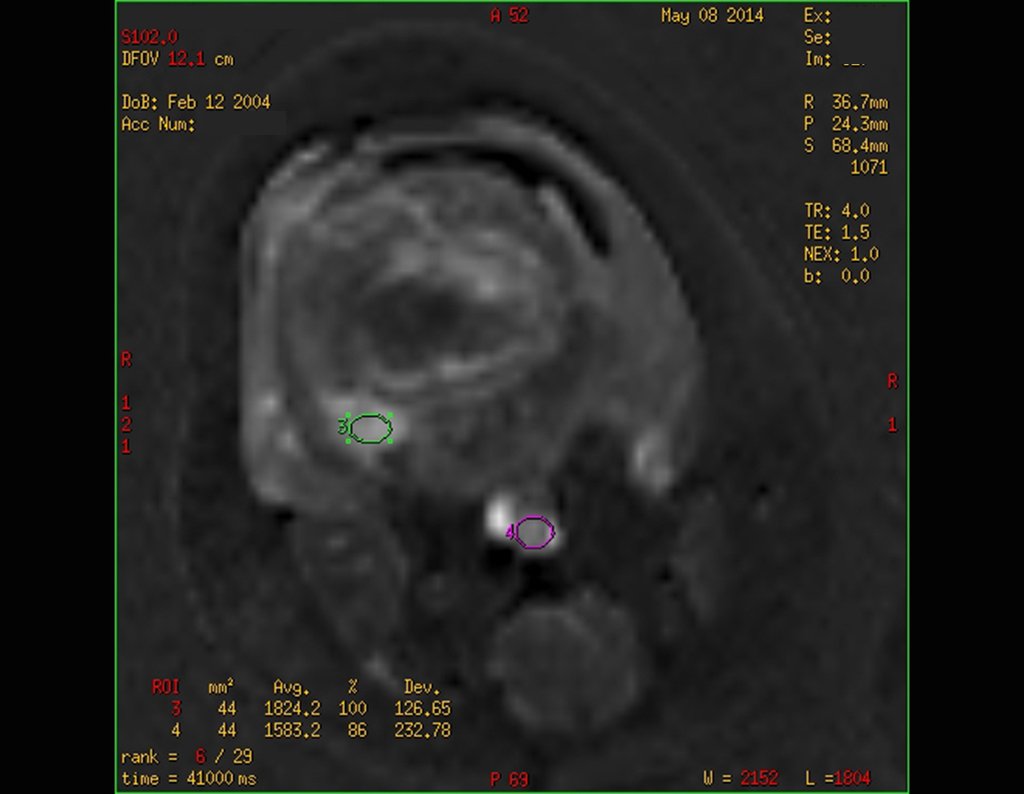

Continuando o estadiamento foi realizada a ressonância magnética, figuras 9 a 18.